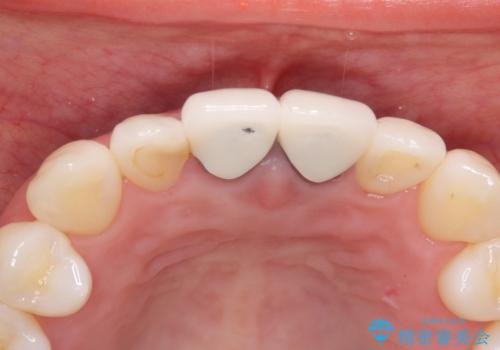

- 10年前ほどに前歯に装着されたセラミックの根元の方が黒くなってきたのが気になるとのことで来院されました。

上顎の前歯の歯茎が下がり、ご自身の歯が露出している状態でした。

金属の土台をファイバーコアに交換後、オールセラミッククラウンを装着する計画としました。